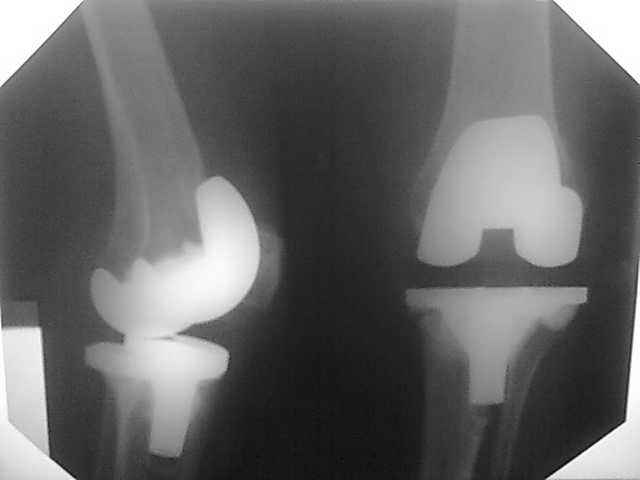

Женщина 1952 г.р., оперирована в 2006, в одной клинике установлен эндопротез правого коленного сустава, через год нестабильность обоих компонентов, доктор выполняет ревизию обычным протезом с задним стабилизатором.

В октябре 2008 - нестабильность, свищ. В другом стационаре все удалено, спейсер с гентамицином, длинный курс антибиотиков.

Коллатеральных связок нет. Собственная связка надколенника цела.

До удаления протеза - выраженная смешанная контрактура.

Планы: Стоит выбор 1) Обычный hinge с цементными ножками, вставками под тибиальным и бедренным компонентами с импакционной костной пластикой аллокостью с применением сеток для удержания трансплантата на tibia; 2) Онкологический hinge - с замещением проксимальной голени и сохранением бедра; 3 - артродез.